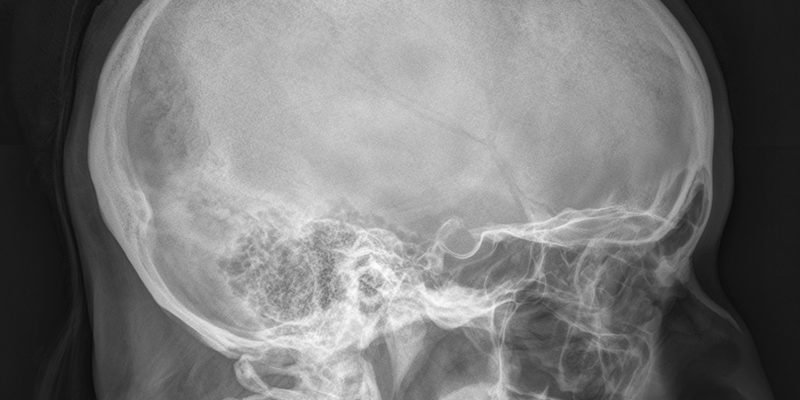

Направление на рентгенологическое обследование турецкого седла выдает эндокринолог, гинеколог, офтальмолог и невролог. Обследование показано для определения состояния гипофиза. Это слизистая железа, расположенная в голове и защищенная от внешних факторов костью, которую называют турецким седлом.

Турецкое седло — это костное образование в форме ямочки, расположенное в подъязычной кости. Его форма напоминает очертания седла — отсюда и название.

В центральной части седла имеется углубление, в котором располагается гипофиз — небольшое уплотнение, свободно расположенное на стержне или ножке железы. Этот элемент эндокринной системы отвечает за выработку гормонов, работу желез внутренней секреции и регулирование обмена веществ.

Часто выполняется дополнительная обзорная рентгенография черепа. Это измерение позволяет определить размер и форму турецкого седла по сравнению с аналогичными характеристиками черепа.

Рентгенологическую карту составляет рентгенолог. Специалист оценивает размерные параметры, форму, контур и состояние костей.